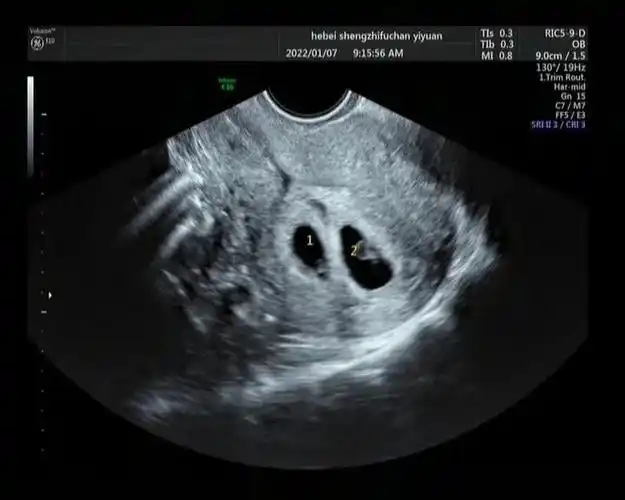

好孕案例六促一移仅有两枚胚胎一次移植成功